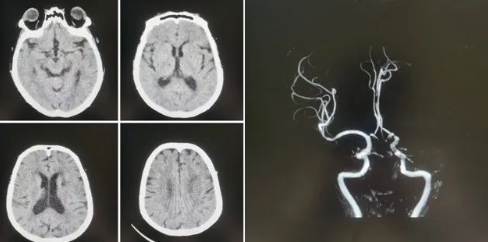

品質(zhì)國文丨國文醫(yī)院神經(jīng)介入科成功實(shí)施高難度機(jī)械取栓術(shù)

近日,國文醫(yī)院神經(jīng)介入科團(tuán)隊(duì)成功實(shí)施了一例高難度的腦血栓機(jī)械取栓術(shù),為一名急性腦梗死患者打通了“生命通道”。這一手術(shù)的成功,不僅標(biāo)志著國文醫(yī)院在急性缺血性腦卒中救治領(lǐng)域的技術(shù)水平邁上了新臺(tái)階,也為區(qū)域卒中中心建設(shè)增添了新的里程碑。 閱讀量:1174